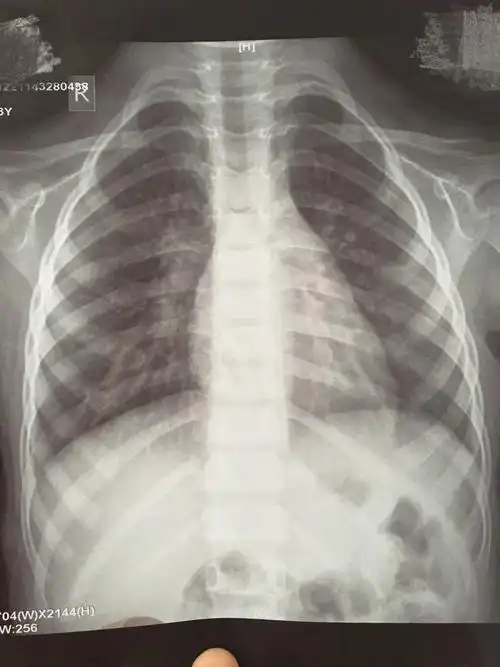

孩子3周岁多点,支气管肺炎入院治疗,6天后,孩子明显好转,医生依然让